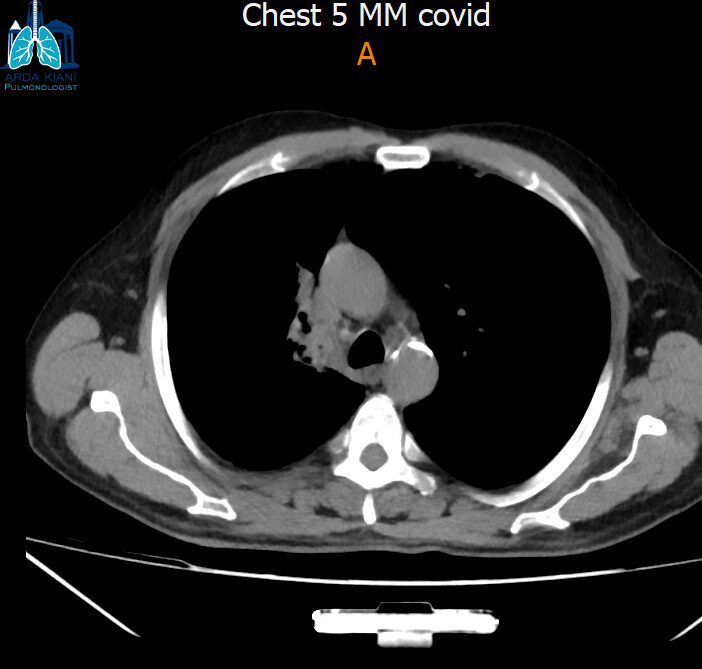

نەخۆشێک کە پێشتر تەنێکی نامۆ لە لوولەی سەرەوەی سییەکانیدا هەبووە، ٣ جار پشکنینی بۆرییەکانی هەناسەی بۆ کراوە و تووشی وەرەمێک بووە، بەڵام دوای ئەنجامدانی پشکنینی بۆرییەکانی هەناسە، بۆمان دەرکەوت کە ئەم تەنە نامۆیە هێلکە بووە.